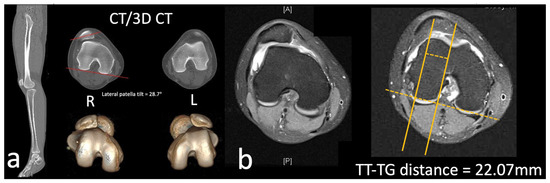

2. Clinical Cases

2.1. Case

3.4. Lateral Patella Tilt